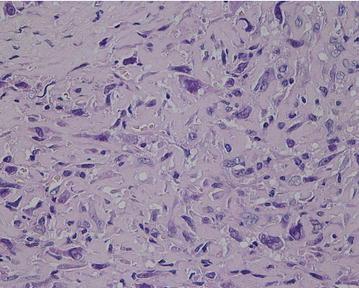

The authors describe clinical and radiologic features, histologic appearance, and treatment of osteogenic osteosarcoma located in the proximal femoral diaphysis associated with an unstable femoral prosthesis following THA in a 65-year-old male patient. The patient with HLA-B27 positive ankylosing spondylitis underwent arthroplasty 15 years ago.